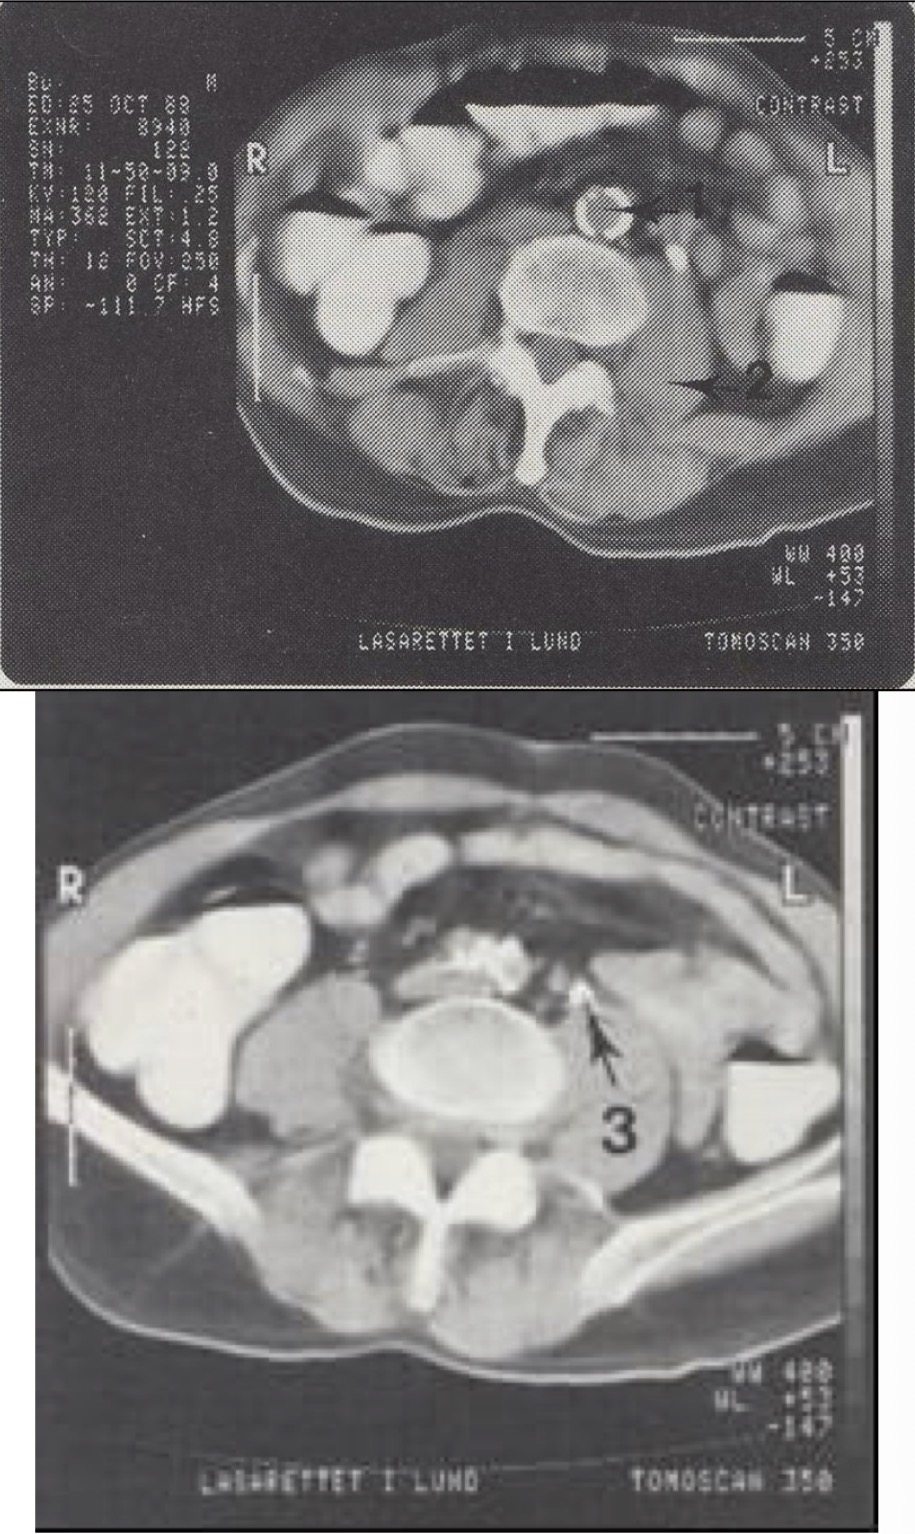

1

Aorta abdominalis (kalcifikuota pilvinė aorta)

2

M. psoas major (didysis juosmens raumuo)

3

Ureter sinister (kairysis šlapimtakis, šiek tiek praplėstas)

Metodika

KT pjūviai nuo juosmens slankstelių iki gaktinės sąvaržos apačios. Suleistas intraveninis kontrastas (išryškina šlapimo takus) ir išgertas kontrastas (išryškina žarnyną).

Radiniai

Gausūs apkalkėjimai (kalcifikatai) aplink pilvinę aortą ir vidines klubo arterijas. Kairysis šlapimtakis matomas priešais m. psoas major, jis šiek tiek išsiplėtęs.